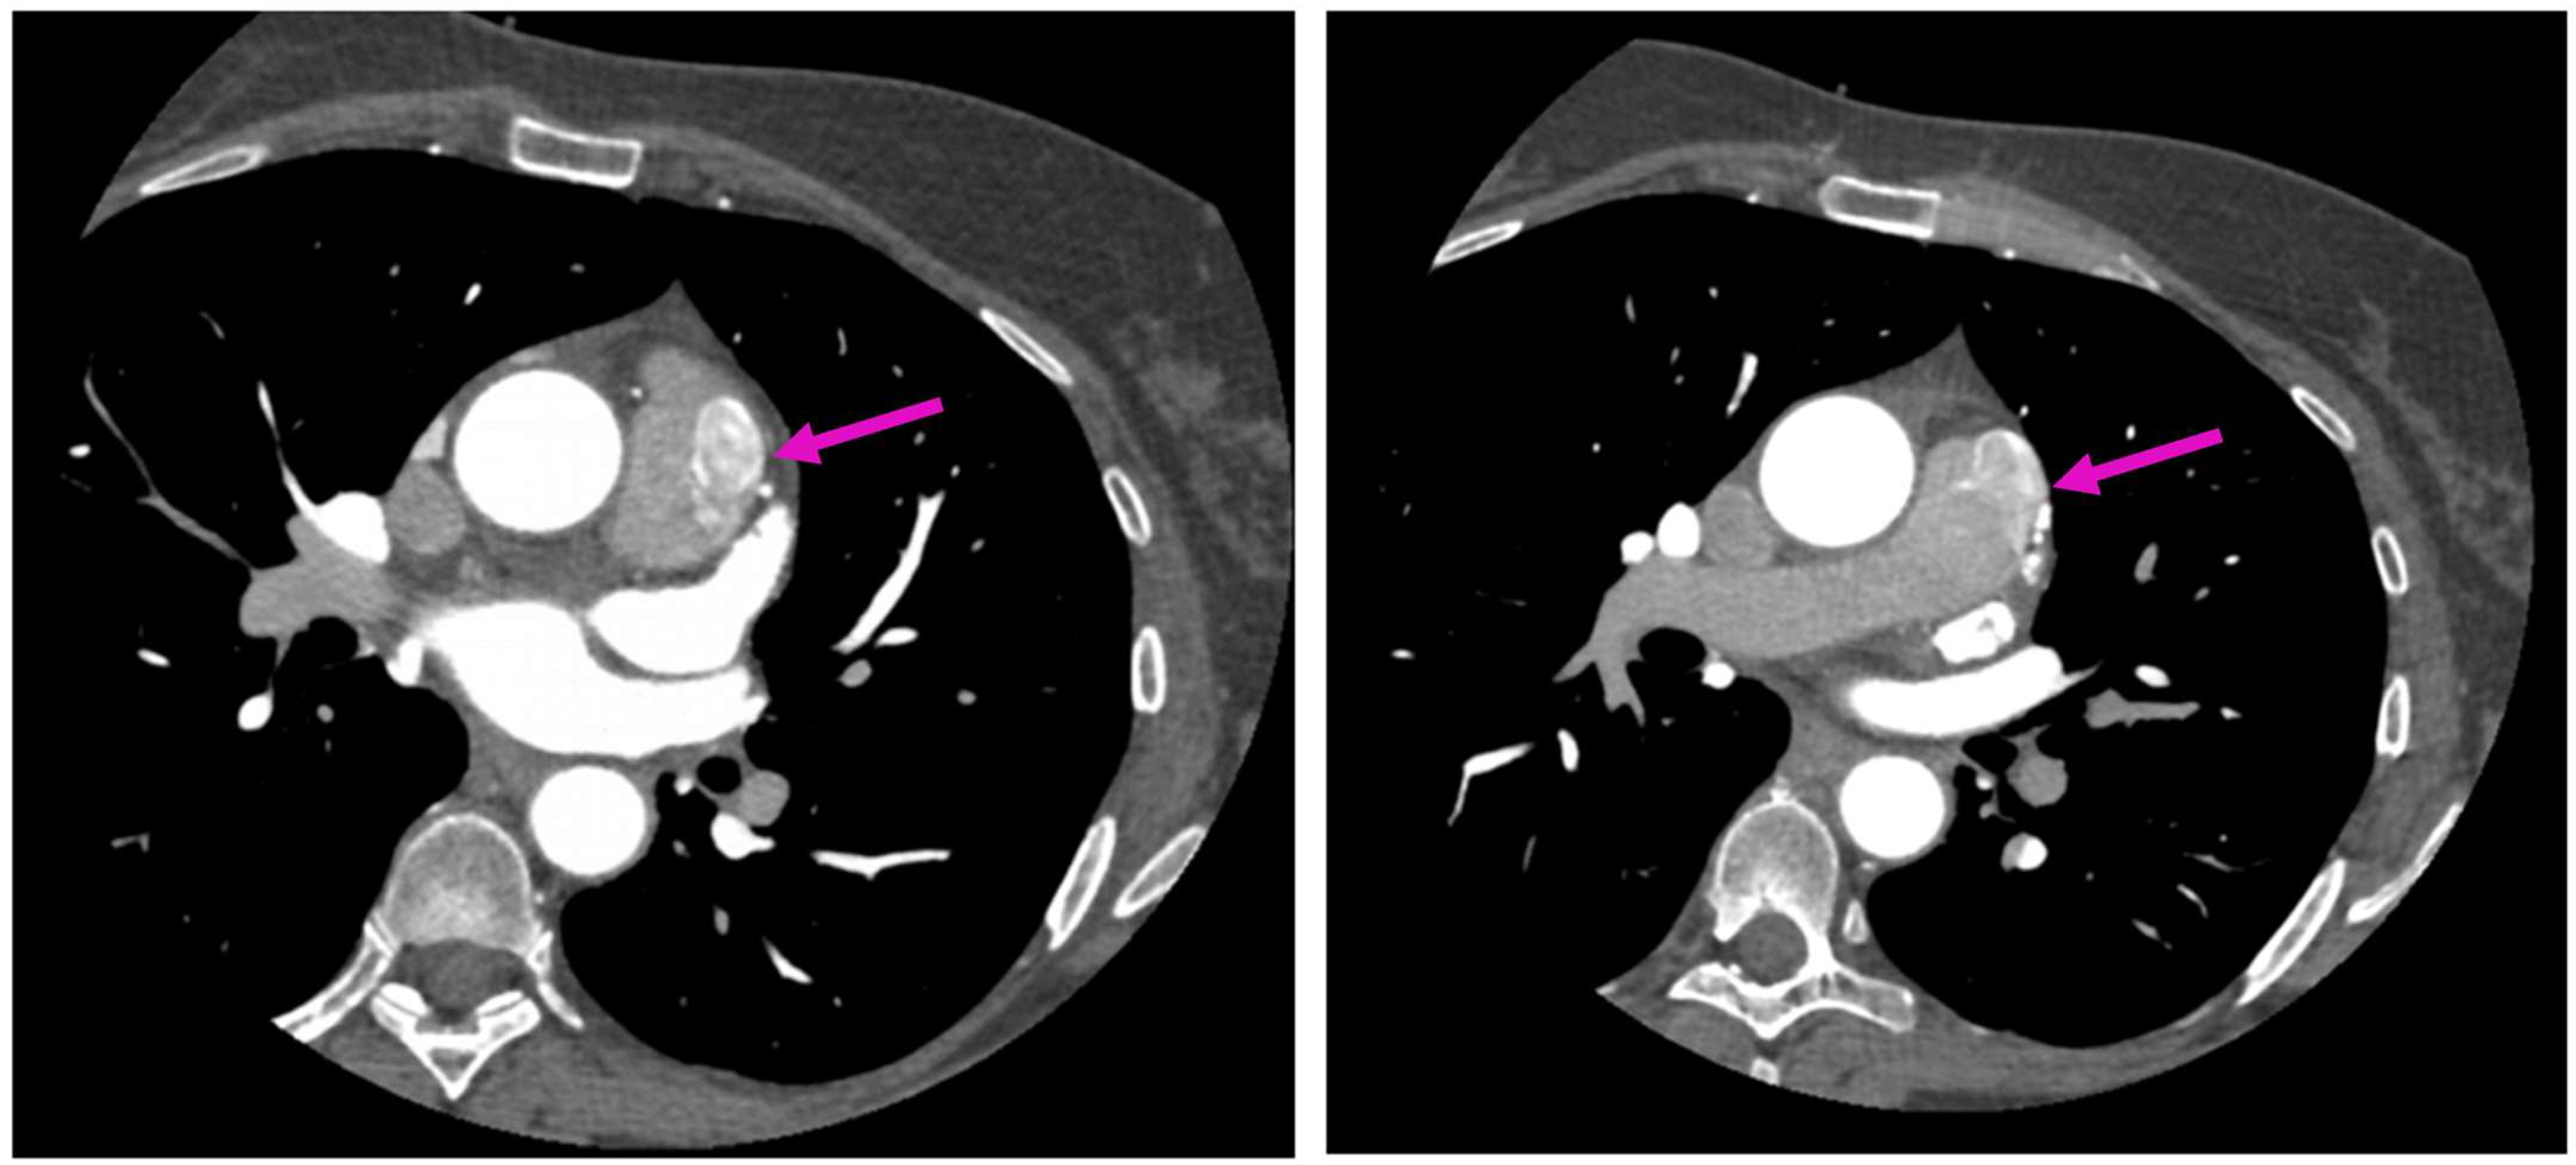

A Rare Case of Left Anterior Descending Coronary Artery to Pulmonary Trunk Fistula Associated with Takotsubo Cardiomyopathy